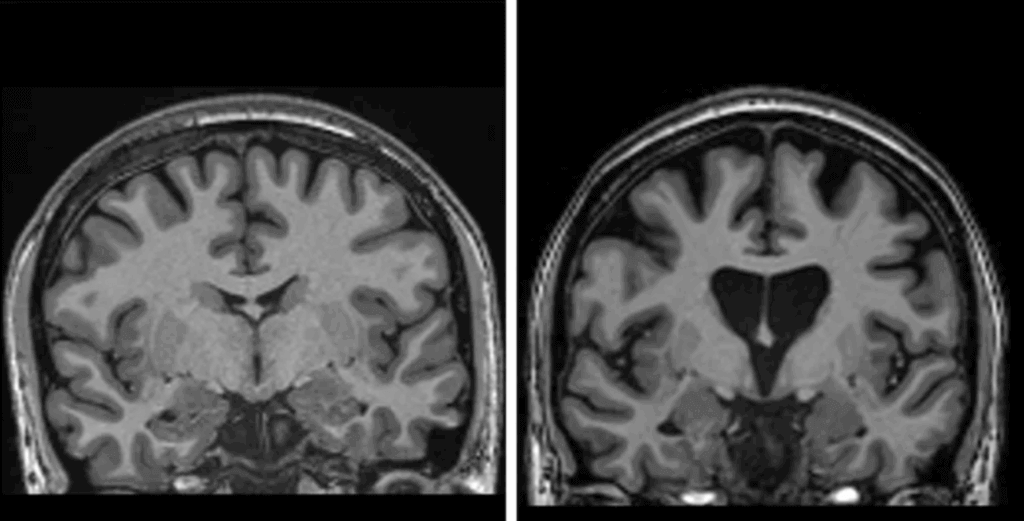

How, exactly, does the therapy work? In short, its goal is to reduce levels of the toxic huntingtin protein permanently, in a single treatment. It starts with a safe, genetically modified virus, AMT-130, that has been altered to contain a specially designed sequence of DNA that is the active agent. But delivering it to the right place is difficult: It requires a surgical operation during which the virus is infused deep into the brain using real-time MRI scanning to guide a microcatheter to two brain regions—the caudate nucleus and the putamen. This typically takes 12–18 hours of neurosurgery.